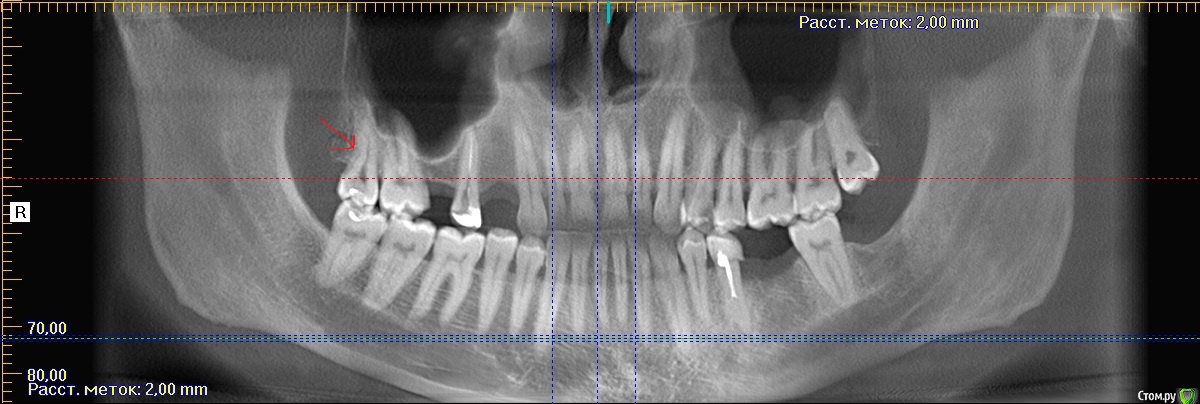

shurkne Опубликовано 7 марта, 2015 Поделиться Опубликовано 7 марта, 2015 (изменено) Скажите удалять ли 1.8 или лечить?глубокий прищечный кариес....пульпит Изменено 7 марта, 2015 пользователем shurkne Ссылка на комментарий

red_butler Опубликовано 7 марта, 2015 Поделиться Опубликовано 7 марта, 2015 а почему не лечить?если сильно хочется, то лечите, по снимку похоже на пульпит, в этом случае протезируйте коронкой. И наладить гигиену. Зуб уже лечен и появился новый кариес, что говорит о огрехах в гигиене. Я бы рекомендовал заниматься участками потерянных зубов, а восьмерку отпустить.Решать Вам Ссылка на комментарий

shurkne Опубликовано 7 марта, 2015 Автор Поделиться Опубликовано 7 марта, 2015 (изменено) если сильно хочется, то лечите, по снимку похоже на пульпит, в этом случае протезируйте коронкой. И наладить гигиену. Зуб уже лечен и появился новый кариес, что говорит о огрехах в гигиене. Я бы рекомендовал заниматься участками потерянных зубов, а восьмерку отпустить.Решать Вамтам две пломбы было...1 вывалилась.....упустил время и проело до пульпы..1.5 тоже недавно удалил.... есть только 1.2.3. 7.8..получается только 1.7 буду жевать Изменено 7 марта, 2015 пользователем shurkne Ссылка на комментарий

red_butler Опубликовано 7 марта, 2015 Поделиться Опубликовано 7 марта, 2015 посмотрите на левую сторону, остался один жевательный зуб, нужно решать более глобальные проблемы - протезироваться.У Вас острая импланто - недостаточность 2 Ссылка на комментарий

red_butler Опубликовано 7 марта, 2015 Поделиться Опубликовано 7 марта, 2015 так на правой тоже получается 1.7 будент жевательным) одним) У Вас острая импланто - недостаточность Ссылка на комментарий